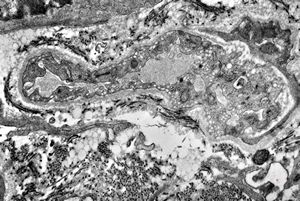

M,60y. | jejunum - amyloidosis